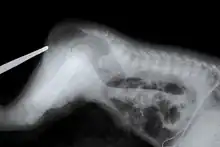

An X-ray showing imperforate anus